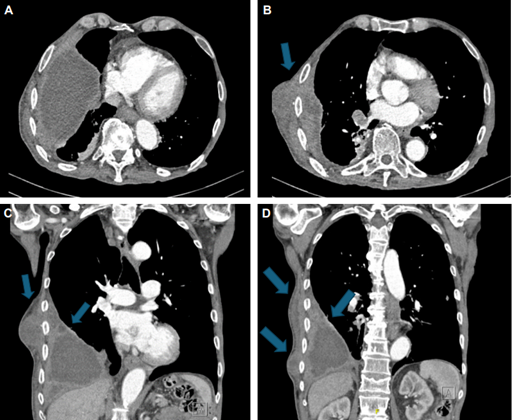

Consultó a nuestra institución por un cuadro de dos a tres semanas de astenia, adinamia, fiebre y pérdida de peso de 19 kg. Además, refería la aparición de dos masas dolorosas en zona lateral de la pared torácica derecha, desde hacía una semana (Figura 1). La ecografía reportó dos lesiones voluminosas con cambios inflamatorios, la menor de las lesiones con una clara comunicación con la cavidad pleural; ambas lesiones tenían líquido de aspecto complicado, probablemente material purulento, por lo que se sospechó un empiema necessitatis. Se solicitó una TC de tórax que informó un empiema derecho con comunicación a la pared torácica, que confirmó la presencia de un empiema necessitatis (Figura 2).

Ante la presencia de los hallazgos clínicos descritos, se puede realizar inicialmente una radiografía de tórax, en donde se observan hallazgos compatibles con derrame pleural y signos de loculación, lo que aumenta la sospecha de un empiema 14. El diagnóstico definitivo se puede realizar con una ecografía de la lesión en la piel, que va a mostrar una colección subcutánea con una clara comunicación al espacio pleural, pero la TC de tórax es la ayuda diagnóstica que mayor rendimiento tiene y que más datos aporta, ya que puede confirmar la presencia de un empiema, puede mostrar claramente la comunicación del líquido con la pared torácica, así como también el engrosamiento pleural, los infiltrados parenquimatosos, u otros hallazgos importantes, como la presencia de nódulos o masas pulmonares 11,15.

En una serie de 9 casos descrita por Akgül AG, et al. 9, encontraron que todos los pacientes con empiema necessitatis tuvieron alguna patología pulmonar como antecedente (tuberculosis pulmonar tratada, neumonía previa, pleuritis crónica o derrame pleural tratado), todos los pacientes se presentaron con un absceso en la pared torácica y todos requirieron algún tipo de drenaje. Los hallazgos más comunes en la TC fueron las atelectasias, infiltrados en el parénquima pulmonar, engrosamiento pleural y la colección con líquido loculado con una comunicación al tejido celular subcutáneo. En 5 pacientes se confirmó la presencia de Mycobacterium tuberculosis y un paciente se diagnosticó con carcinoma escamocelular de pulmón 9.